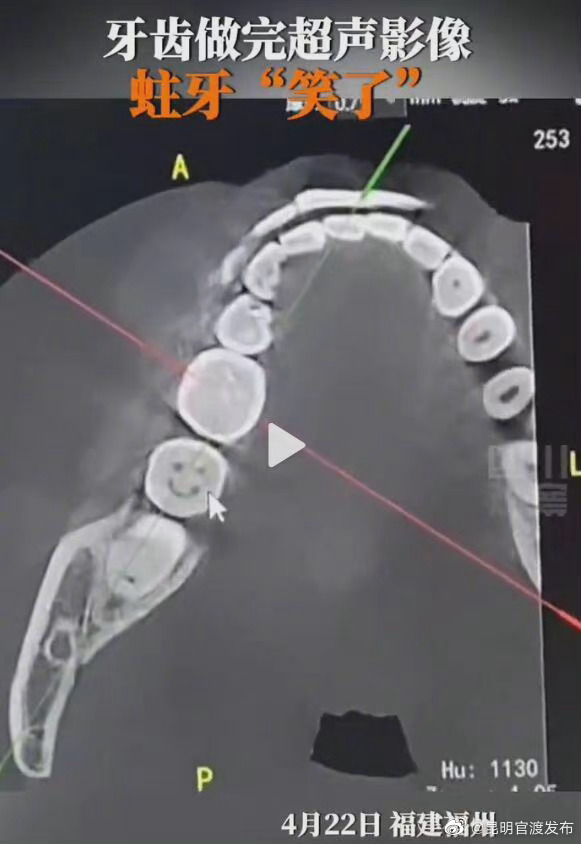

福建一女子#拍牙齿CT发现蛀牙蛀成一张笑脸#,一时不知道该哭还是该笑。牙齿变黑到脱落只需4步:表面出现黑褐色小点或细线→牙齿表面可出现黑洞→攻向牙髓,冷热温度刺激出现疼痛→引发牙髓炎、根尖周炎等,甚至造成牙齿脱落。注意保护牙齿,否则蛀牙就要对你“微笑”了↓(生命时报)